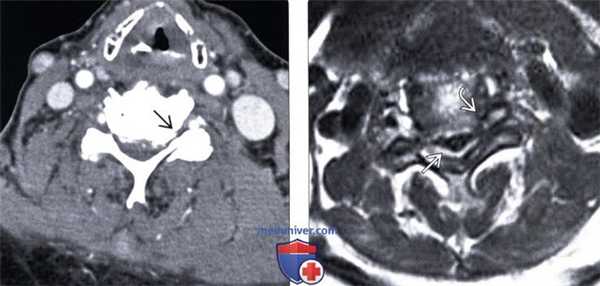

(Слева) КТ с КУ, аксиальный срез: признаки тяжелого стеноза спинномозгового канала на фоне диффузного пролабирования межпозвонкового диска с вентральными грыжами и кальцификацией диска. Видны признаки выраженного двустороннего фораминального стеноза, гипертрофии унковертебральных суставов и дегенерации дугоотростчатых суставов.

(Справа) Т2-ВИ, аксиальная проекция: выраженное истончение спинного мозга, проявляющееся относительным усилением сигнала и связанное с его импинджментом между межпозвонковым диском и остеофитами вентрально и утолщенной отличающейся низкой интенсивностью сигнала желтой связкой дорзально. Также видны признаки выраженного двустороннего фораминального стеноза.

(Слева) На аксиальной КТ с КУ определяется тяжелый стеноз позвоночного канала, обусловленный диффузными грыжами диска на широком основании с сопутствующим обызвествлением диска. Определяется также выраженный двухсторонний стеноз межпозвонковых отверстий в сочетании с гипертрофией унковертебральных суставов и дегенеративными изменениями суставных отростков.

(Справа) На аксиальной MPT (Т2 ВИ) определяется выраженное истончение спинною мозга с относительно гиперинтенсивным сигналом, ограниченною спереди диском и остеофитами, сзади - утолщенными желтыми связками с гипоинтенсивным сигналом. Определяется выраженный стеноз обоих межпозвонковых отверстий.